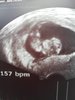

Ale jeszcze nie wiem czy pozytywna? Przeciez L ma 1000 ml wiec chyba musze podzielic i wychodzi 0.2 na ml to chyba sie nie udalo? Do lekarza nie moge sie dodzwonic jezu umre zarazCudowny tydzien[emoji173] gruba bedziesz

Sliczna beta[emoji173][emoji173][emoji173]